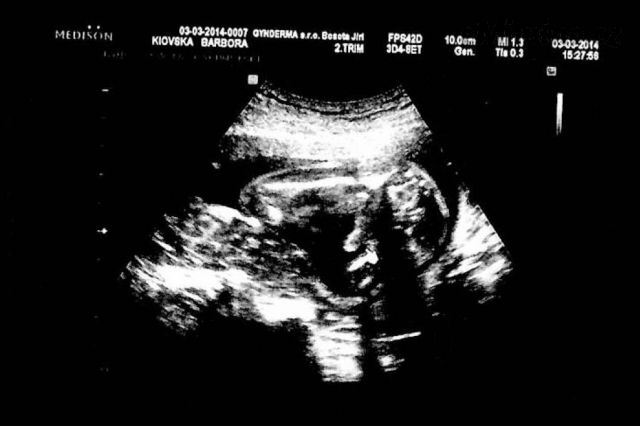

no tam kde je ta šipka tak to je prý penis? a to na těch stranách jsou stehna

[473297]já to tam prostě nevidím, na našem je krásné "kávové zrno", takže u nás je to na 100 % holčička